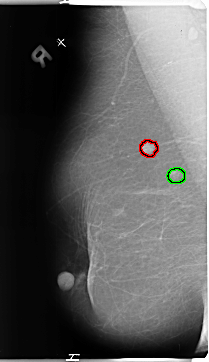

FILE: B_3135_1.RIGHT_MLO.OVERLAY

TOTAL_ABNORMALITIES 2

ABNORMALITY 1

LESION_TYPE MASS SHAPE IRREGULAR MARGINS SPICULATED

ASSESSMENT 4

SUBTLETY 5

PATHOLOGY MALIGNANT

ABNORMALITY 2

LESION_TYPE MASS SHAPE IRREGULAR MARGINS ILL_DEFINED

SUBTLETY 4

PATHOLOGY UNPROVEN